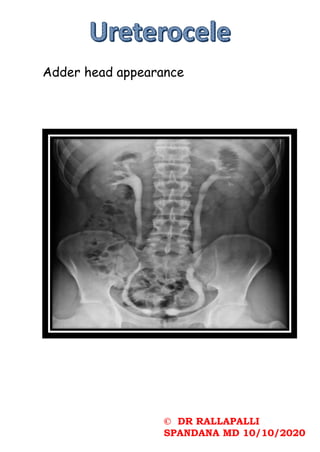

Adder head appearance

© DR RALLAPALLI SPANDANAMD 10/10/2020 Adder head appearance